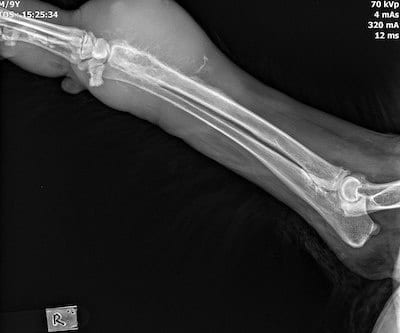

A radiograph of the affected area is shown below.

This is a classic image of osteosarcoma, a common, aggressive bone tumor typically found in the appendicular skeleton, especially distal radius.

Usually, does not cross joint (unlike osteomyelitis, which usually does cross joint). Look for soft tissue swelling, periosteal proliferation, sunburst periosteal reaction (33%), possible pathologic fractures.